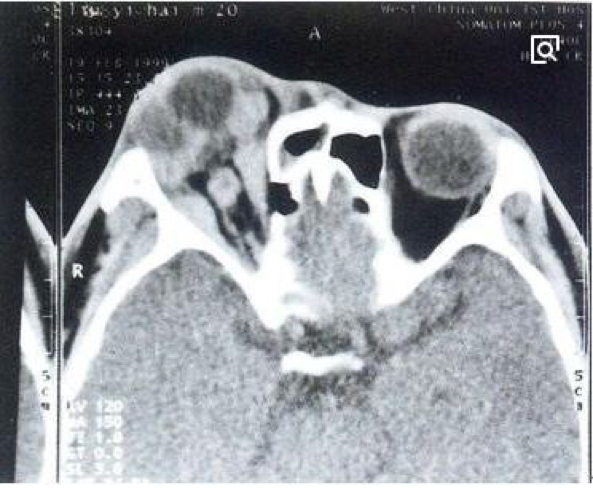

2.炎性假瘤 是指炎性增生时形成境界清楚的瘤样肿块,常发生于眼眶和肺。组织学上炎性假瘤由肉芽组织、炎细胞、增生的实质细胞及纤维组织构成。X线检查时,其外形与肿瘤结节相似,因而被称之为炎性假瘤,应注意与真性肿瘤鉴别。 |